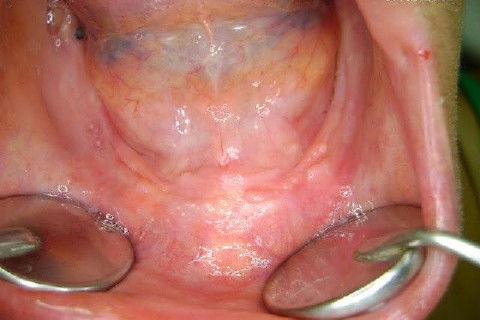

Apesar da boa adaptação e estética satisfatória, a principal queixa da paciente era a instabilidade da prótese inferior, como sempre ocorre nestes casos...atrofia do rebordo alveolar e perda da função mastigatória.